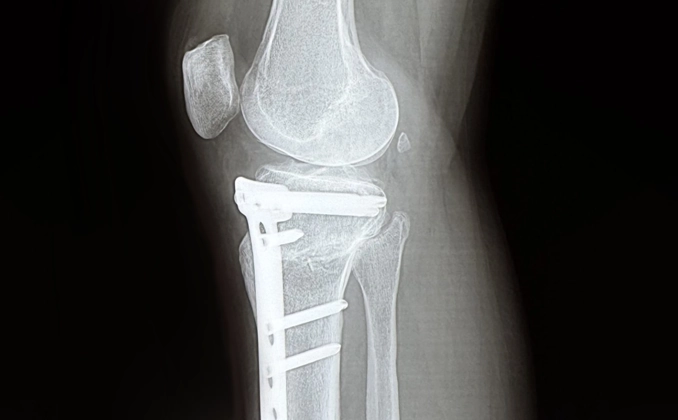

Коригуюча остеотомія проводиться під загальним або регіонарним наркозом і зазвичай триває 1,5–2 години. Хірург виконує розріз у ділянці гомілки або стегна, після чого проводить опил кістки. Після корекції кута фрагменти фіксуються спеціальними пластинами та гвинтами, що забезпечують стабільність і правильне положення. Для контролю точності процедури використовується рентген-контроль.

У деяких випадках через 12–24 місяці після операції може бути рекомендоване видалення металевих конструкцій, однак більшість пацієнтів живе з ними без дискомфорту.